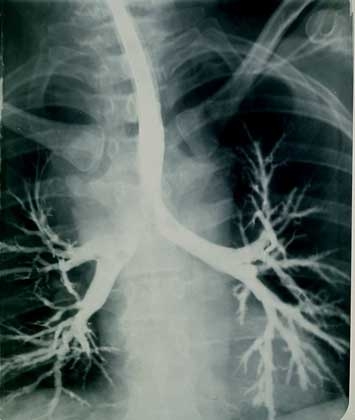

На рентгенограммах легких (преимущественно в нижних и средних отделах) определяются нежная диффузная сетчатость и мелкая ячеистость. Узелки локализуются в нижних отделах легких. Нередко обнаруживают плевральные сращения.